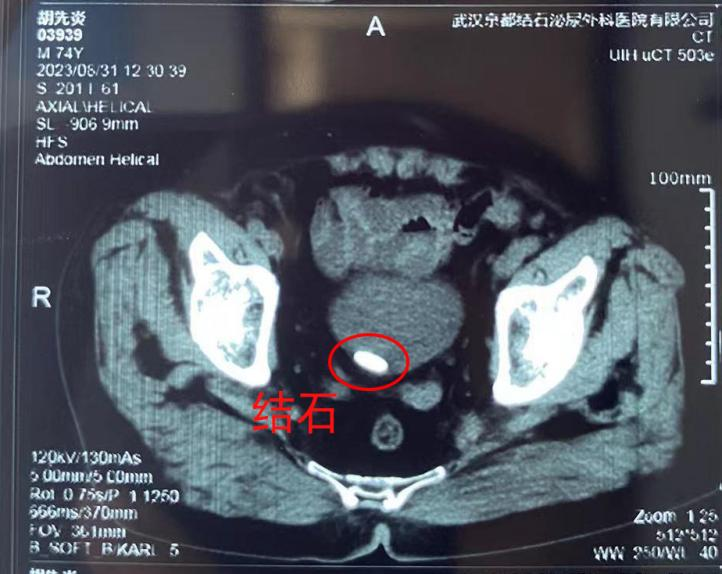

檢查結(jié)果提示,胡爹爹膀胱內(nèi)的結(jié)石直徑接近3公分,同時(shí)還有前列腺增生的問(wèn)題??紤]到爹爹年紀(jì)較大,且基礎(chǔ)疾病較多,該院醫(yī)生在多科會(huì)診后,決定為其定制并實(shí)施無(wú)創(chuàng)取石的手術(shù)方案。經(jīng)過(guò)1個(gè)多小時(shí),爹爹膀胱內(nèi)的大結(jié)石被順利取出。因?yàn)槿虩o(wú)創(chuàng),術(shù)后恢復(fù)得很快,對(duì)這樣輕松的手術(shù)經(jīng)歷打破了他對(duì)傳統(tǒng)手術(shù)的認(rèn)知,不禁連連向醫(yī)生豎起了大拇指。